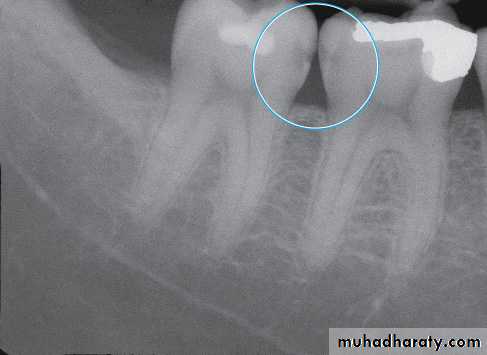

Radiograph of occlusal caries. This radiograph shows (1) severe occlusal caries, which appears as a large radiolucent lesion in the first molar

• Dental Caries